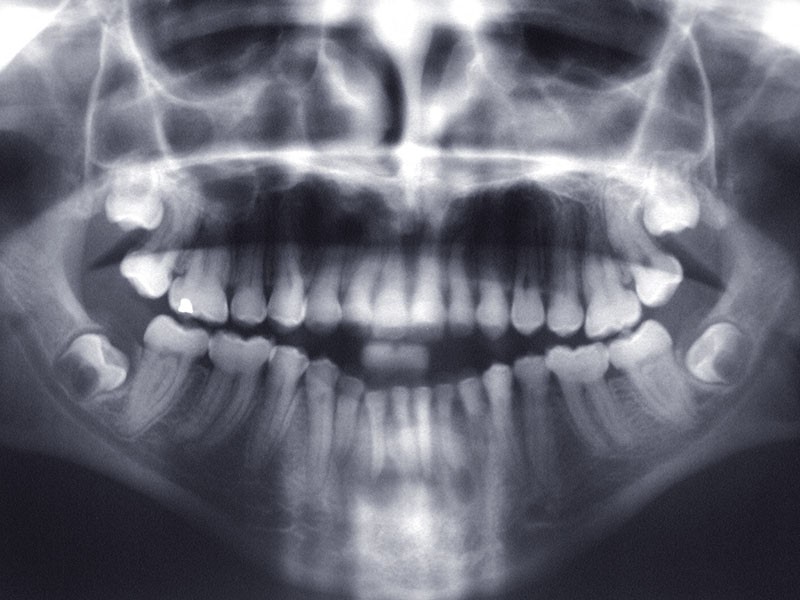

Teinte opalescente grise à jaune ambrée, couronnes globuleuses, calcifications intra-pulpaires, racines fines et courtes, attrition précoce, nécrose aseptique… Ces anomalies cliniques et radiographiques décrivent le tableau de la dentinogenèse imparfaite (DI) isolée de type 2. Cette anomalie génétique à transmission autosomique dominante est liée à un défaut de DSPP, gène de la sialophosphoprotéine dentinaire [1, 2]. Des anomalies dentinaires similaires résultent également de mutations de ce gène. Les avancées en recherche génétique tendent à réunir ces pathologies sous une même étiologie.